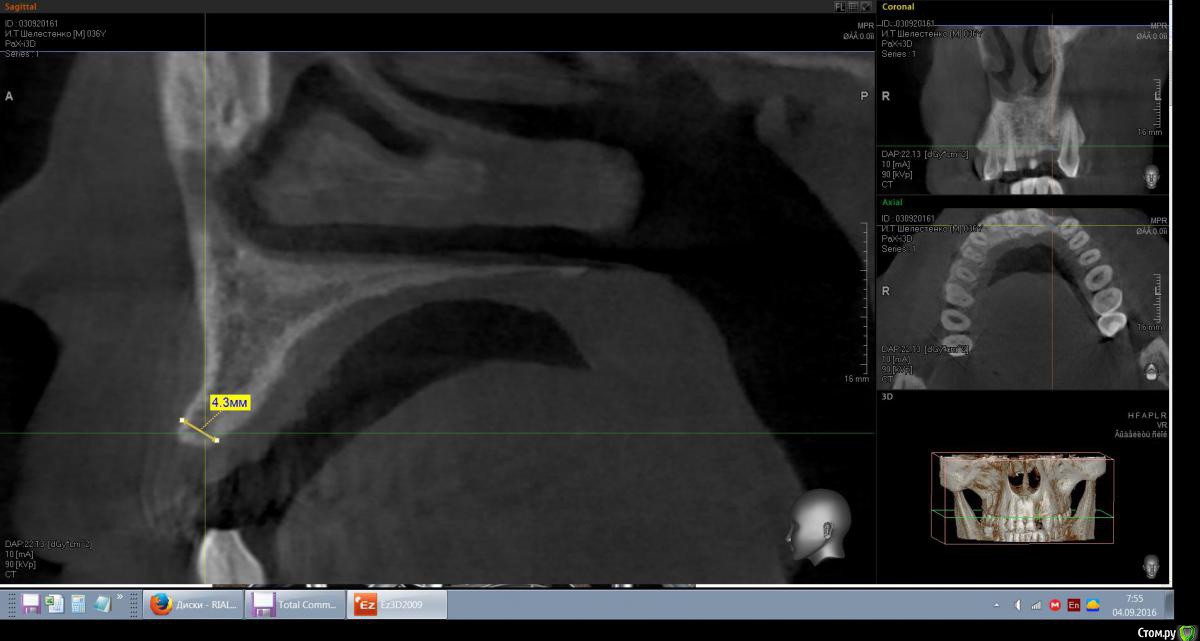

mann Опубликовано 4 сентября, 2016 Автор Поделиться Опубликовано 4 сентября, 2016 Доброе утро!Имеем такую ситуацию. Как лучше и правильно расположить имплант в данной ситуции? Ссылка на комментарий

red_butler Опубликовано 4 сентября, 2016 Поделиться Опубликовано 4 сентября, 2016 вот видите костное предложение на самом деле лучше. Только не нужно так небно ставить. Если сомневаетесь сделайте шаблон или пригласите на операцию ортопеда. И трансп добавьте. Ссылка на комментарий

red_butler Опубликовано 4 сентября, 2016 Поделиться Опубликовано 4 сентября, 2016 а что это? трансплантат.Мне больше нравится позиция на втором снимке, только вестибулярнее и не так глубоко, и я бы ложе готовил эспандерами или чуток расщепился бы Ссылка на комментарий

Эдгар Витальевич Опубликовано 22 октября, 2016 Поделиться Опубликовано 22 октября, 2016 Имплант 3.5мм не узковат будет? Такая же операция предстоит, ширина кости также 4.5 мм. Я планировал 4 мм ставить и костную пластику-титановую мембранку на имплант закрепить под фрмирователь. Ссылка на комментарий